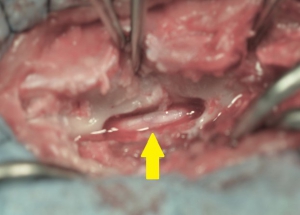

下の写真は片側椎弓切除術(ヘミラミネクトミー)を実施した後の術中写真です。黄色矢印が、椎弓(背骨の一部)を切除して減圧された脊髄です。内部に見られる白い棒状のものが脊髄神経です。この写真では脊髄を圧迫していた物質は既に除去されております。